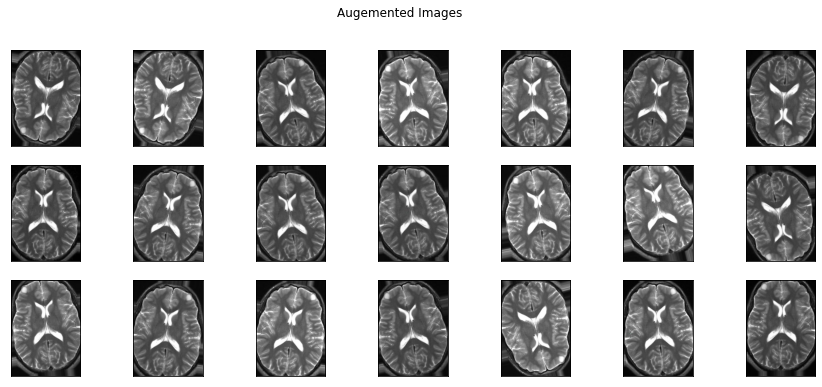

학습해야 할 이미지의 수가 부족하다면 개수를 증가(augmentation) 시켜야 해요! 사람이 보는 이미지와 컴퓨터가 인식하는 이미지는 약간의 차이가 있어요! 아래의 이미지를 보면 (flip, rotation, shear, crop)총 4가지의 방법으로 이미지를 지지고 볶고 해 두었는데요. 사람이 보았을 때는 전부 다 동일한 이미지지만, ‘0’과 ‘1’로 받아들이는 컴퓨터의 입장에서는 모두 다른 이미지로 인식해요!!